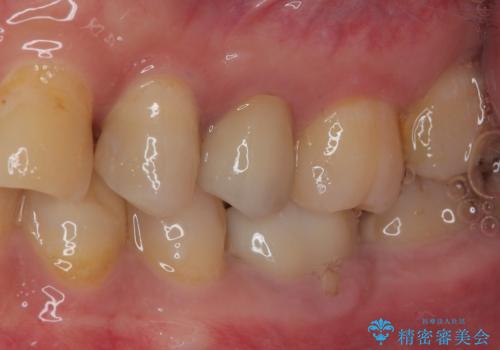

違和感がなくなり、フロスも引っかからなくなり大変喜んでいただけました。

今後左上の4番目の保険診療にて治療を行っている部位についてもセラミックインレー修復を行っていく予定です。